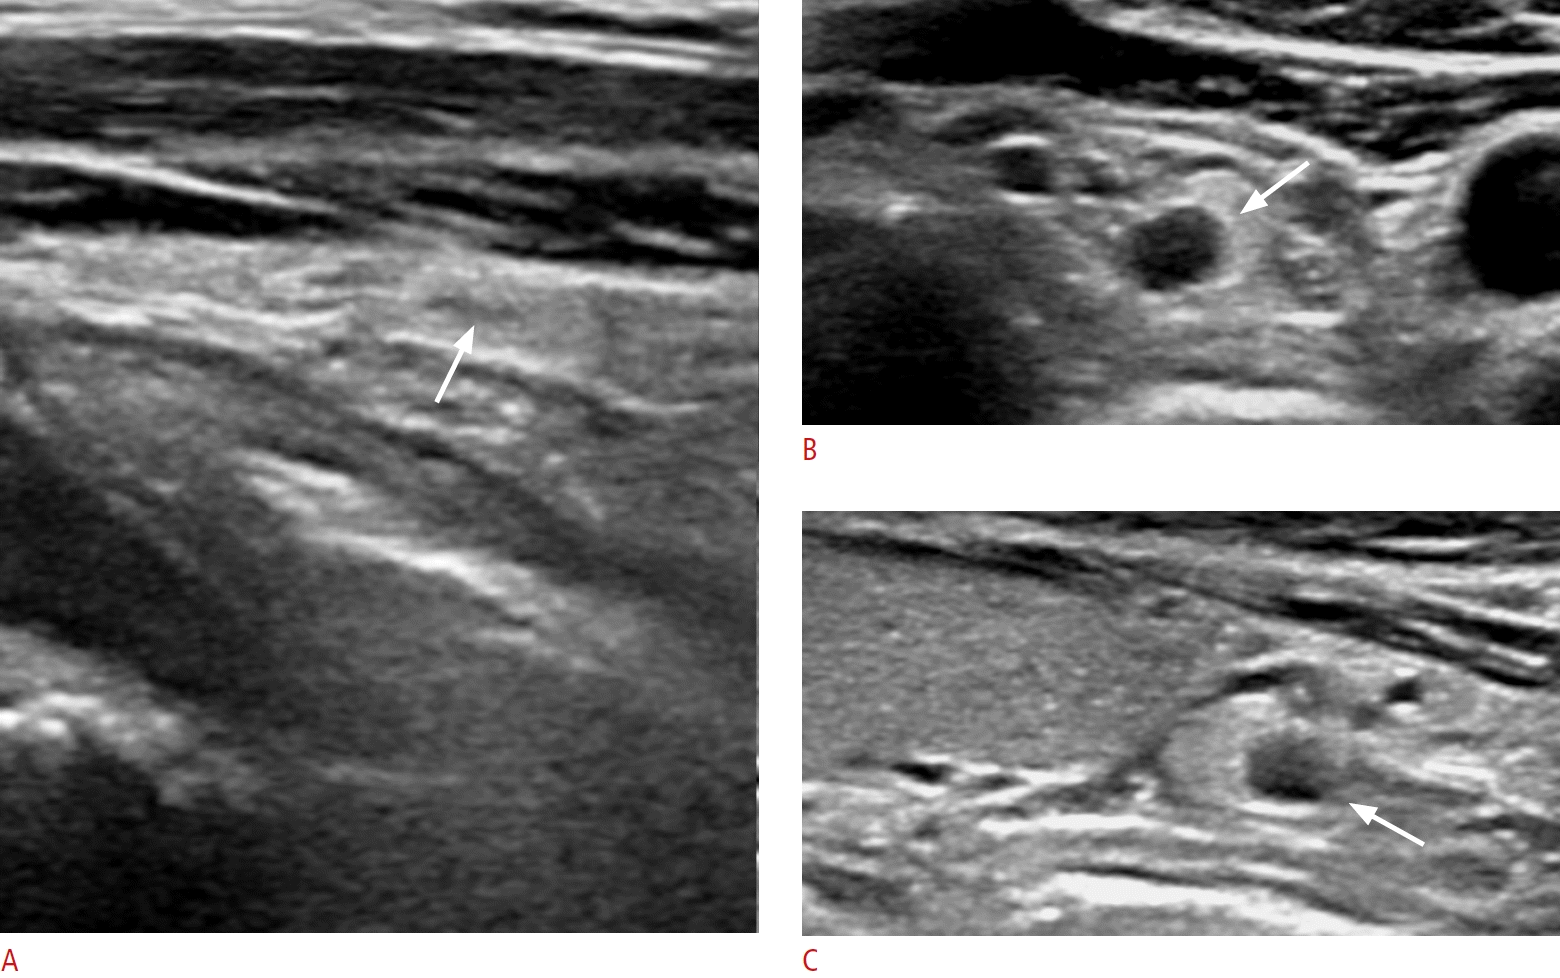

Fig. 5.

Normal parathyroid glands with focal hypoechoic lesions (cases 7 and 8).

A. A longitudinal image shows an ovoid, markedly hyperechoic parathyroid gland with central linear mild hypoechogenicity (arrow) in the left infrathyroid central neck in a 44-year-old female patient. B, C. Transverse and longitudinal images show a round, markedly hyperechoic parathyroid gland with a small, round, anechoic cystic lesion with posterior acoustic enhancement (arrows) at the inferior pole of the left thyroid gland in a 49-year-old male patient. The intraglandular cystic lesion was identified as a parathyroid cyst showing clear fluid on fine needle aspiration.